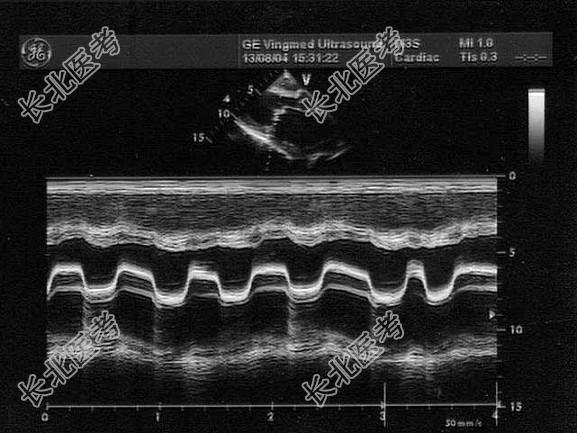

- 单项选择题该病例最有可能诊断为(   )

A、主动脉瓣关闭不全

B、左房黏液瘤

C、二尖瓣关闭不全

D、二尖瓣狭窄

E、二尖瓣脱垂